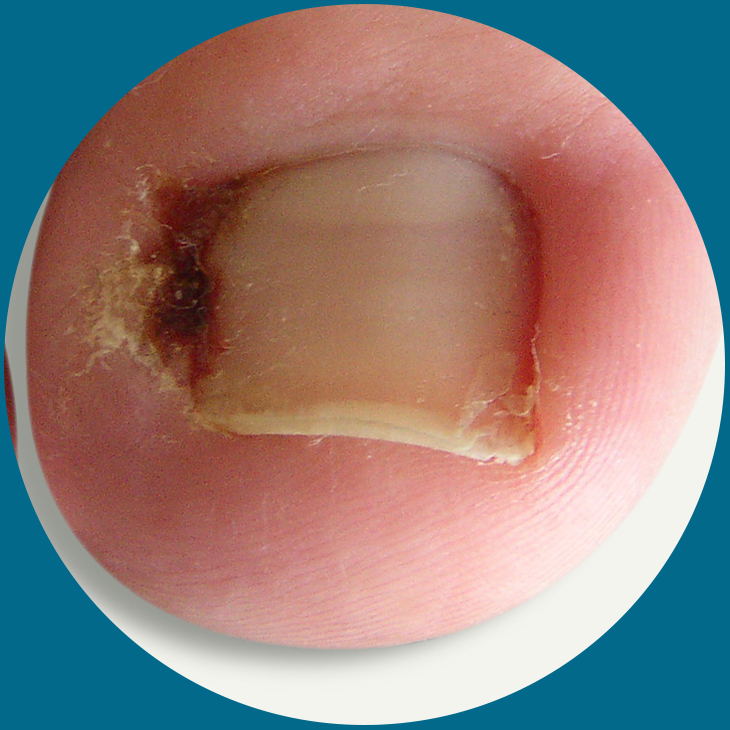

Fungal Nails

Fungal nails cause dramatic visual changes to a nail which can be unsightly. They can make the nail change colour, can thicken and can break more easily. They can cause more pressure on the end of the toe and can become painful. As the fungal infection progresses they can produce a very distinct odour.

Fungal nails infection (onychomycosis) is very common, particularly in the toenails. Around half of all nail problems are due to fungal nail infection. It usually affects adults, and affects more men than women. It also becomes more common as you get older.

There are several types of fungus that cause nail infections. For example, athlete’s foot is a fungal skin infection of the toes, which easily spreads to the toenails. Candida is a yeast which can cause an infection of the skin around the nails, usually the fingernails.

Fungal nails cause dramatic visual changes to a nail which can be unsightly. They can make the nail change colour, can thicken and can break more easily. They can cause more pressure on the end of the toe and can become painful. As the fungal infection progresses they can produce a very distinct odour.

Fungal nails infection (onychomycosis) is very common, particularly in the toenails. Around half of all nail problems are due to fungal nail infection. It usually affects adults, and affects more men than women. It also becomes more common as you get older.

There are several types of fungus that cause nail infections. For example, athlete’s foot is a fungal skin infection of the toes, which easily spreads to the toenails. Candida is a yeast which can cause an infection of the skin around the nails, usually the fingernails.